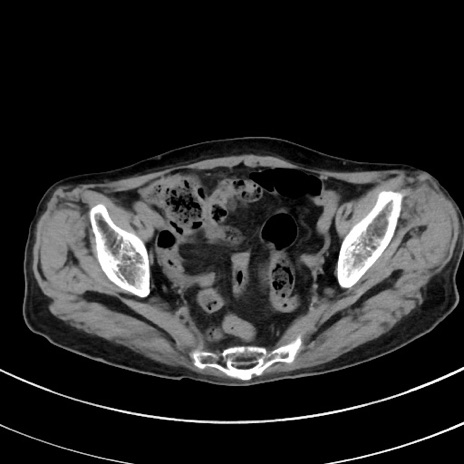

症例33(横断像)

【症例】70歳代 女性

【主訴】心窩部痛

【現病歴】延髄病変の精査・加療にて神経内科入院中。本日より心窩部痛あり。

【既往歴】虫垂炎

【身体所見】右下腹部を中心に圧痛と反跳痛あり。

【データ】WBC 10900、CRP 0.02